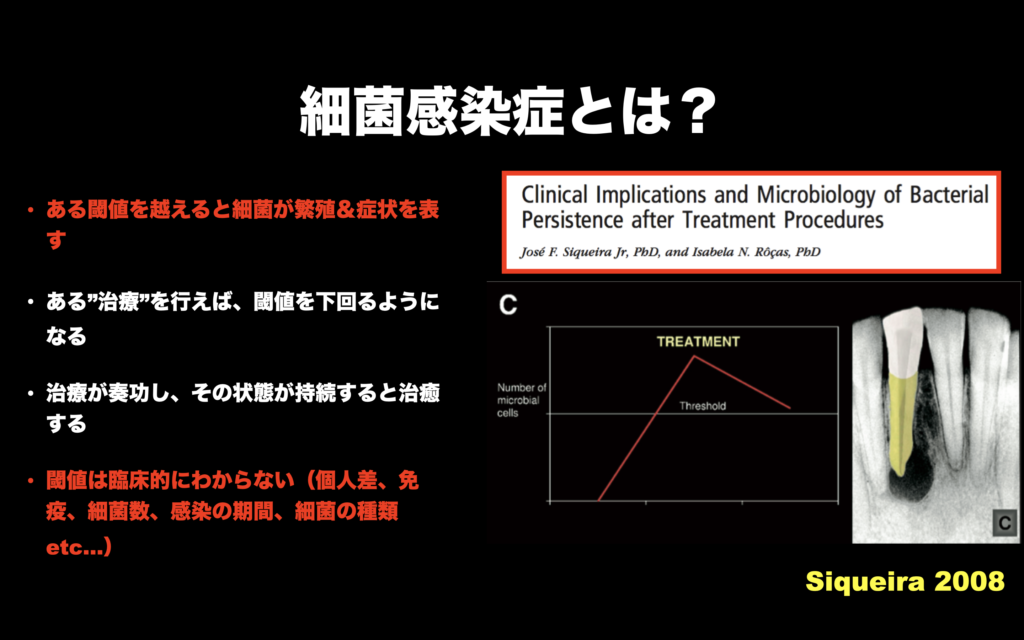

それが可能かどうか?は、

患者さんの免疫力と、

患者さんが持つ細菌の毒性と、

患者さんの細菌に対する抵抗力

等で決まるので神に委ねなければならない。